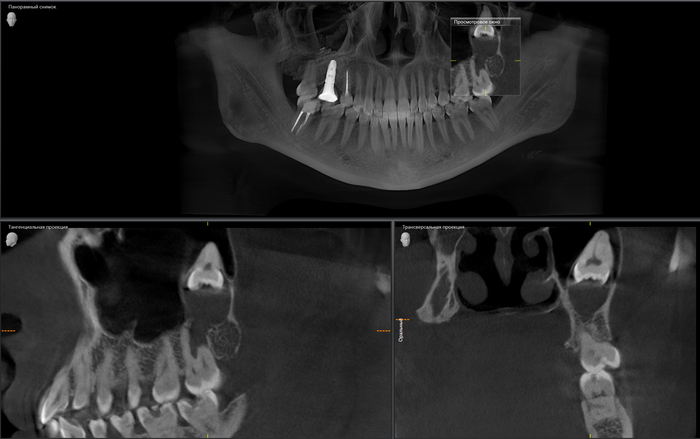

Время нещадно и неумолимо проносится, пациентка приходит в очередной раз на осмотр, ассистентка делает снимок и…

Добрый вечер… А что это значит?... Прекрасно видно, что фолликулярная киста начала расти и оттеснять зуб мудрости дальше в пазуху, что несколько затрудняет его удаление. Блять, подумал я, надо было сразу удалять.

Контрольный снимок после удаления: